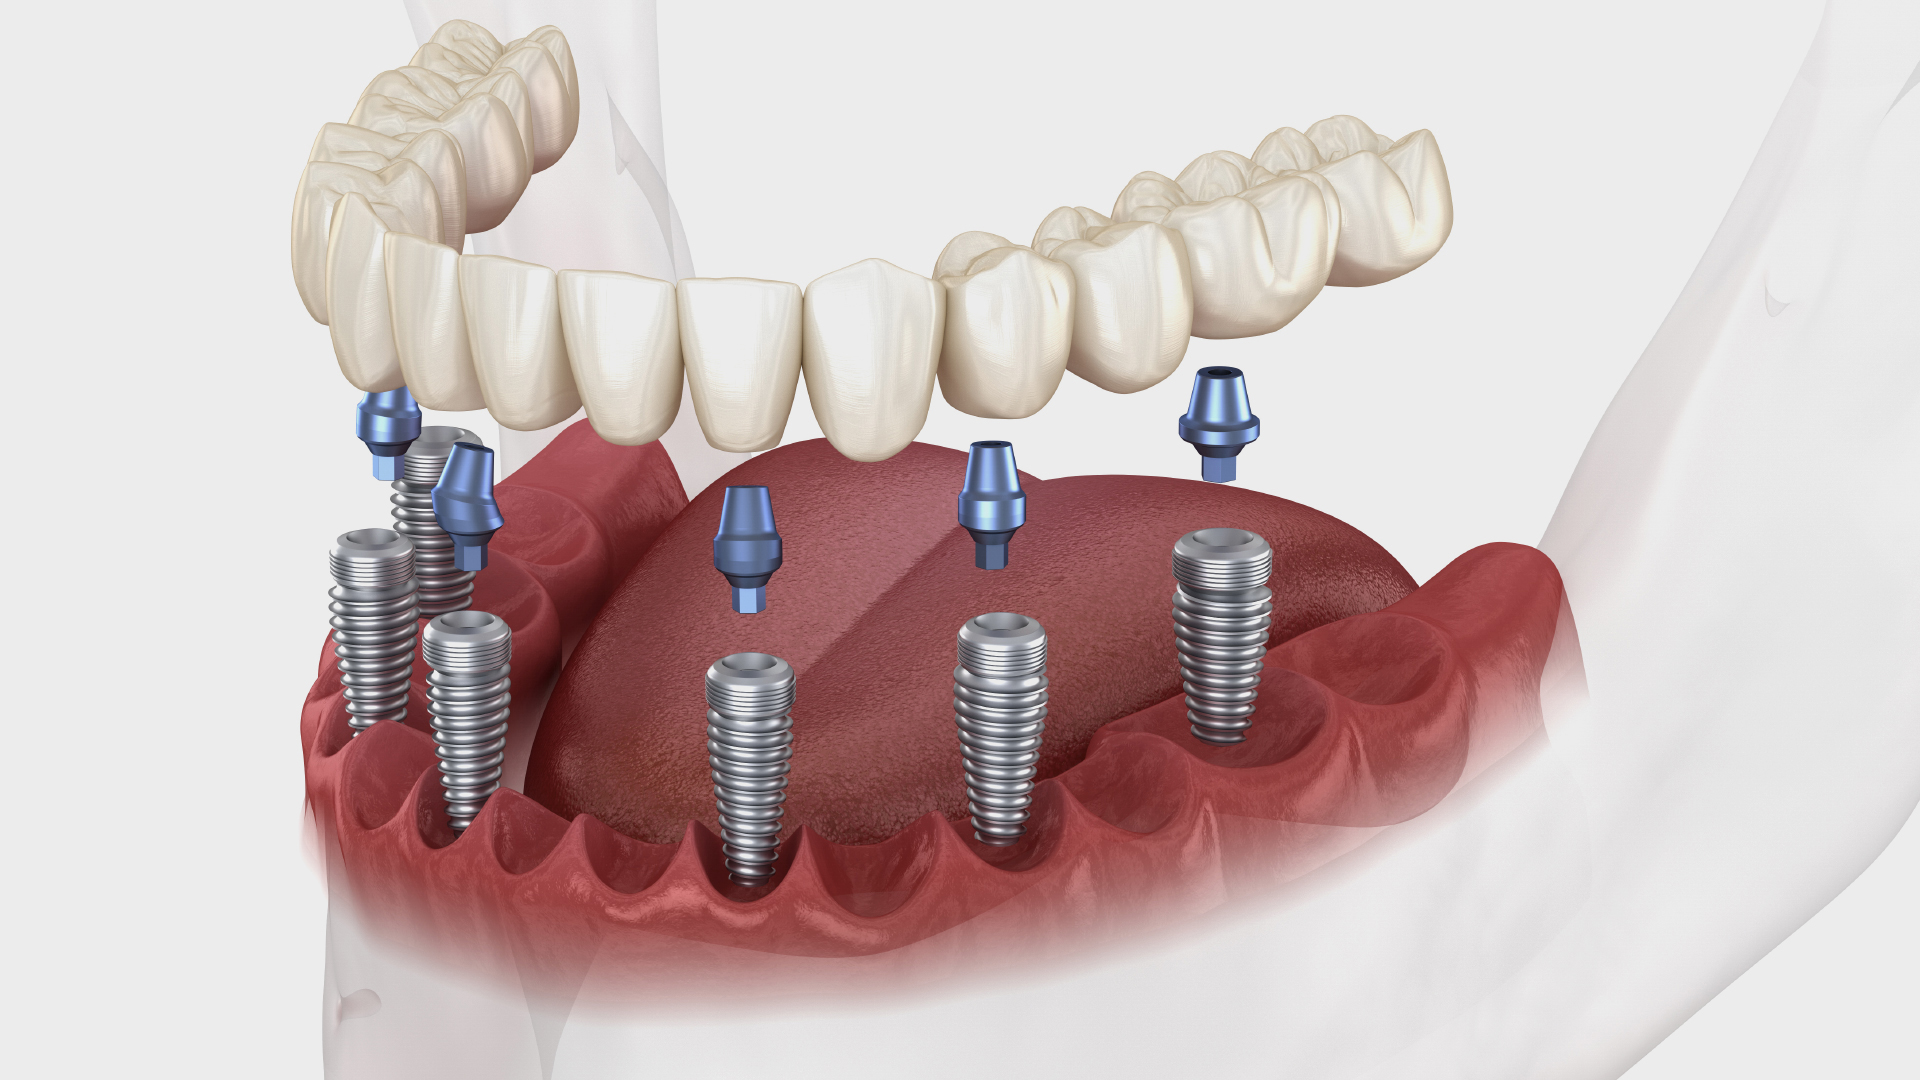

Best for multiple missing teeth or loose dentures. We place implants in stronger bone areas and give fixed teeth for suitable cases. Local anesthesia keeps you comfortable during treatment.

Get dental implants even with low bone. Advanced techniques avoid bone grafting and reduce treatment time.

Get fixed teeth without bone grafting in suitable cases. Simple plan. Comfortable procedure. Clear recovery.

For the back upper jaw. These implants use strong bone at the back to support fixed teeth. This can reduce the need for sinus lift in suitable cases.

For advanced bone loss. Basal implants anchor in dense cortical bone for strong stability. Suitable cases may get fixed teeth faster with fewer surgical steps.

Many patients think they must do bone grafting first. Some cases can avoid that with graftless implants. You get a safety first plan, comfort focused treatment, and a clear timeline. Every case is different, so we confirm suitability with a 3D scan before treatment.